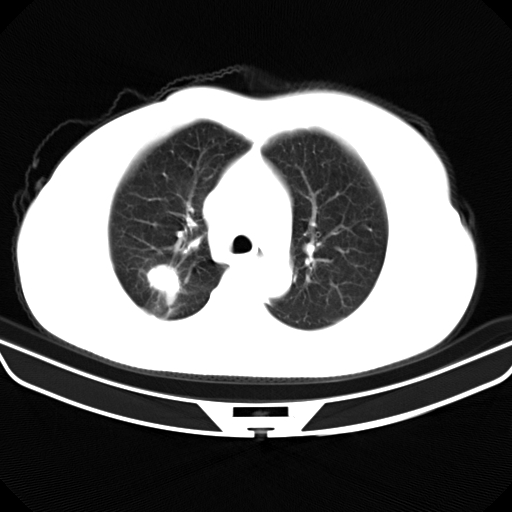

以下是引用zjzjr在2007-3-23 13:28:00的发言:[br]右肺上叶后段可见一结节状高密度影,可见毛刺征,胸膜凹陷征及血管导入征,纵隔内可见肿大淋巴结影.考虑右肺上叶周围型肺癌伴纵隔淋巴结转移.

以下是引用zjzjr在2007-3-23 13:28:00的发言:[br]右肺上叶后段可见一结节状高密度影,可见毛刺征,胸膜凹陷征及血管导入征,气管前腔静脉后可见肿大淋巴结影.考虑右肺上叶周围型肺癌伴纵隔淋巴结转移.